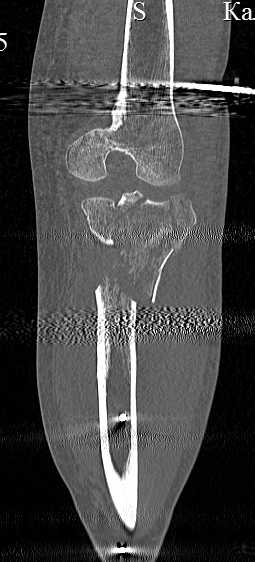

[Ortho] перелом проксимальной тибии + вывих бедра

Серия КТ сканов в аппарате